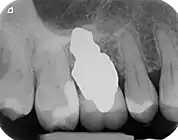

RAIs are custom made to perfectly fit the tooth socket of a specific patient immediately after tooth extraction. Therefore every implant is unique. As an optimized root-form it is much more than a simple 1:1 replica of a tooth. Since it exactly fills the gap left after the tooth is extracted, surgery is rarely needed. The implant can be produced from a copy of the extracted tooth, an impression of the tooth socket, or from a CT scan or CBCT scan.[3] The advantage of a CBCT scan is that the implant can be produced before extraction. With the former methods, it takes one or two days to fabricate an implant.

A root analogue implant can be fabricated from zirconium dioxide (zirconia) or titanium. Successful titanium RAIs have been three-dimensionally printed as porous one-piece implants, using CAD software.[4] However, zirconia is the preferred material, because it is more esthetic in color, with no grey discoloration visible through gums.[5][1]

- Natural form: a custom milled anatomic implant replicates the natural form of a tooth, so it simply fits into the tooth socket. Like the original tooth, a root analogue implant can have single- and multi-rooted forms.

- Esthetic: a ceramic RAI closely resembles a natural tooth in color. Thus there is no discoloration through the gums, as is commonly seen with titanium implants.